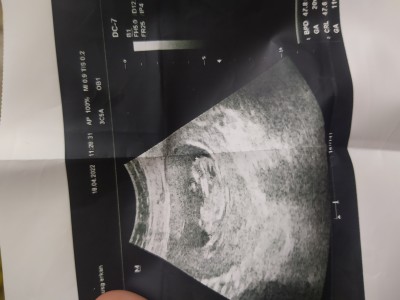

Kızlar CRL DEN  bebeğin cinsiyetini anlayabilir misiniz. 12 haftadayiz. Develete gittiğim için bakmadı tabi . CRL 59.7 NT 0.87

Gebelik haftası 12+1

Yyükledim bakarmısın

image